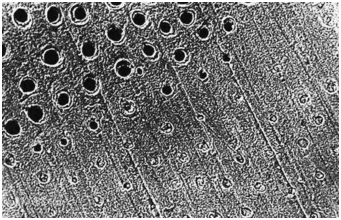

牙本质切削后牙本质纵断面,可见牙本质小管中存在玷污层栓(放大倍数2000)

图中上半部分牙本质采用37%磷酸酸蚀15秒彻底冲洗后牙本质横断面,可见玷污层已经被去除(放大倍数1000)